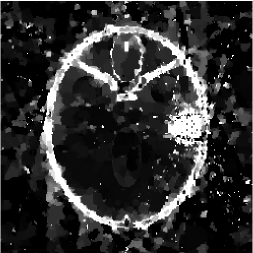

Figures 4 and 5 present visual reconstruction results of the SL phantom and the FB phantom, respectively, both under high additive Gaussian noise (). In particular, Figure 4 is to recover the SL phantom using 7 radial lines. The model has severe streaking artifacts due to this extremely small number of data obtained on the radial lines. The minimization on the gradient yields significant improvements over the baseline model (TV). The proposed algorithm outperforms the previous ADMM approach at the outer ring and boundaries of the three middle oval shapes, which are more obvious in the difference map to the ground truth. On the other hand, the FB phantom has finer structures and lower image contrast compared to the SL phantom. As a result, it requires 13 radial lines for a reasonable reconstruction. As we observe in Figure 5, the overall geometric shapes are preserved. At the same time, many speckle artifacts appear in the reconstructed images by no matter which algorithm is used.